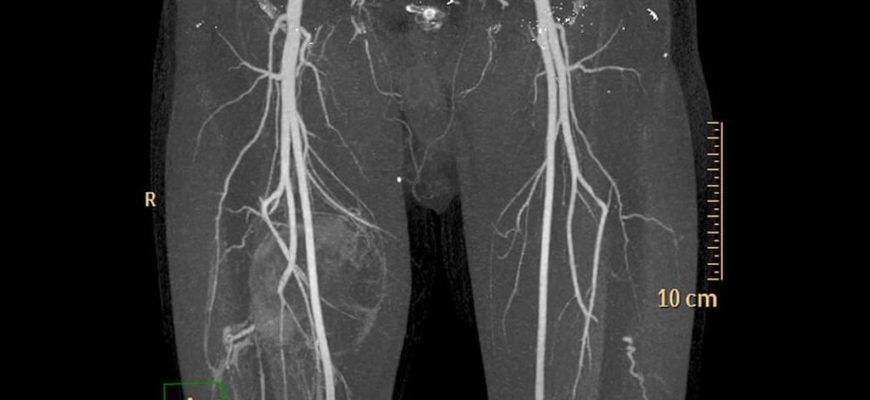

КТА нижних конечностей

БА делится на два основных ствола, общие подвздошные артерии, которые, в свою очередь, делятся на внутренние и внешние подвздошные артерии. Наружная подвздошная артерия переходит в бедренную артерию.

Бедренная артерия ответвляется от бедренной артерии и снабжает кровью глубокие ткани бедра. Бедренная артерия переходит в подколенную артерию на уровне коленного сустава. Подколенная артерия делится на переднюю и заднюю большеберцовые артерии.